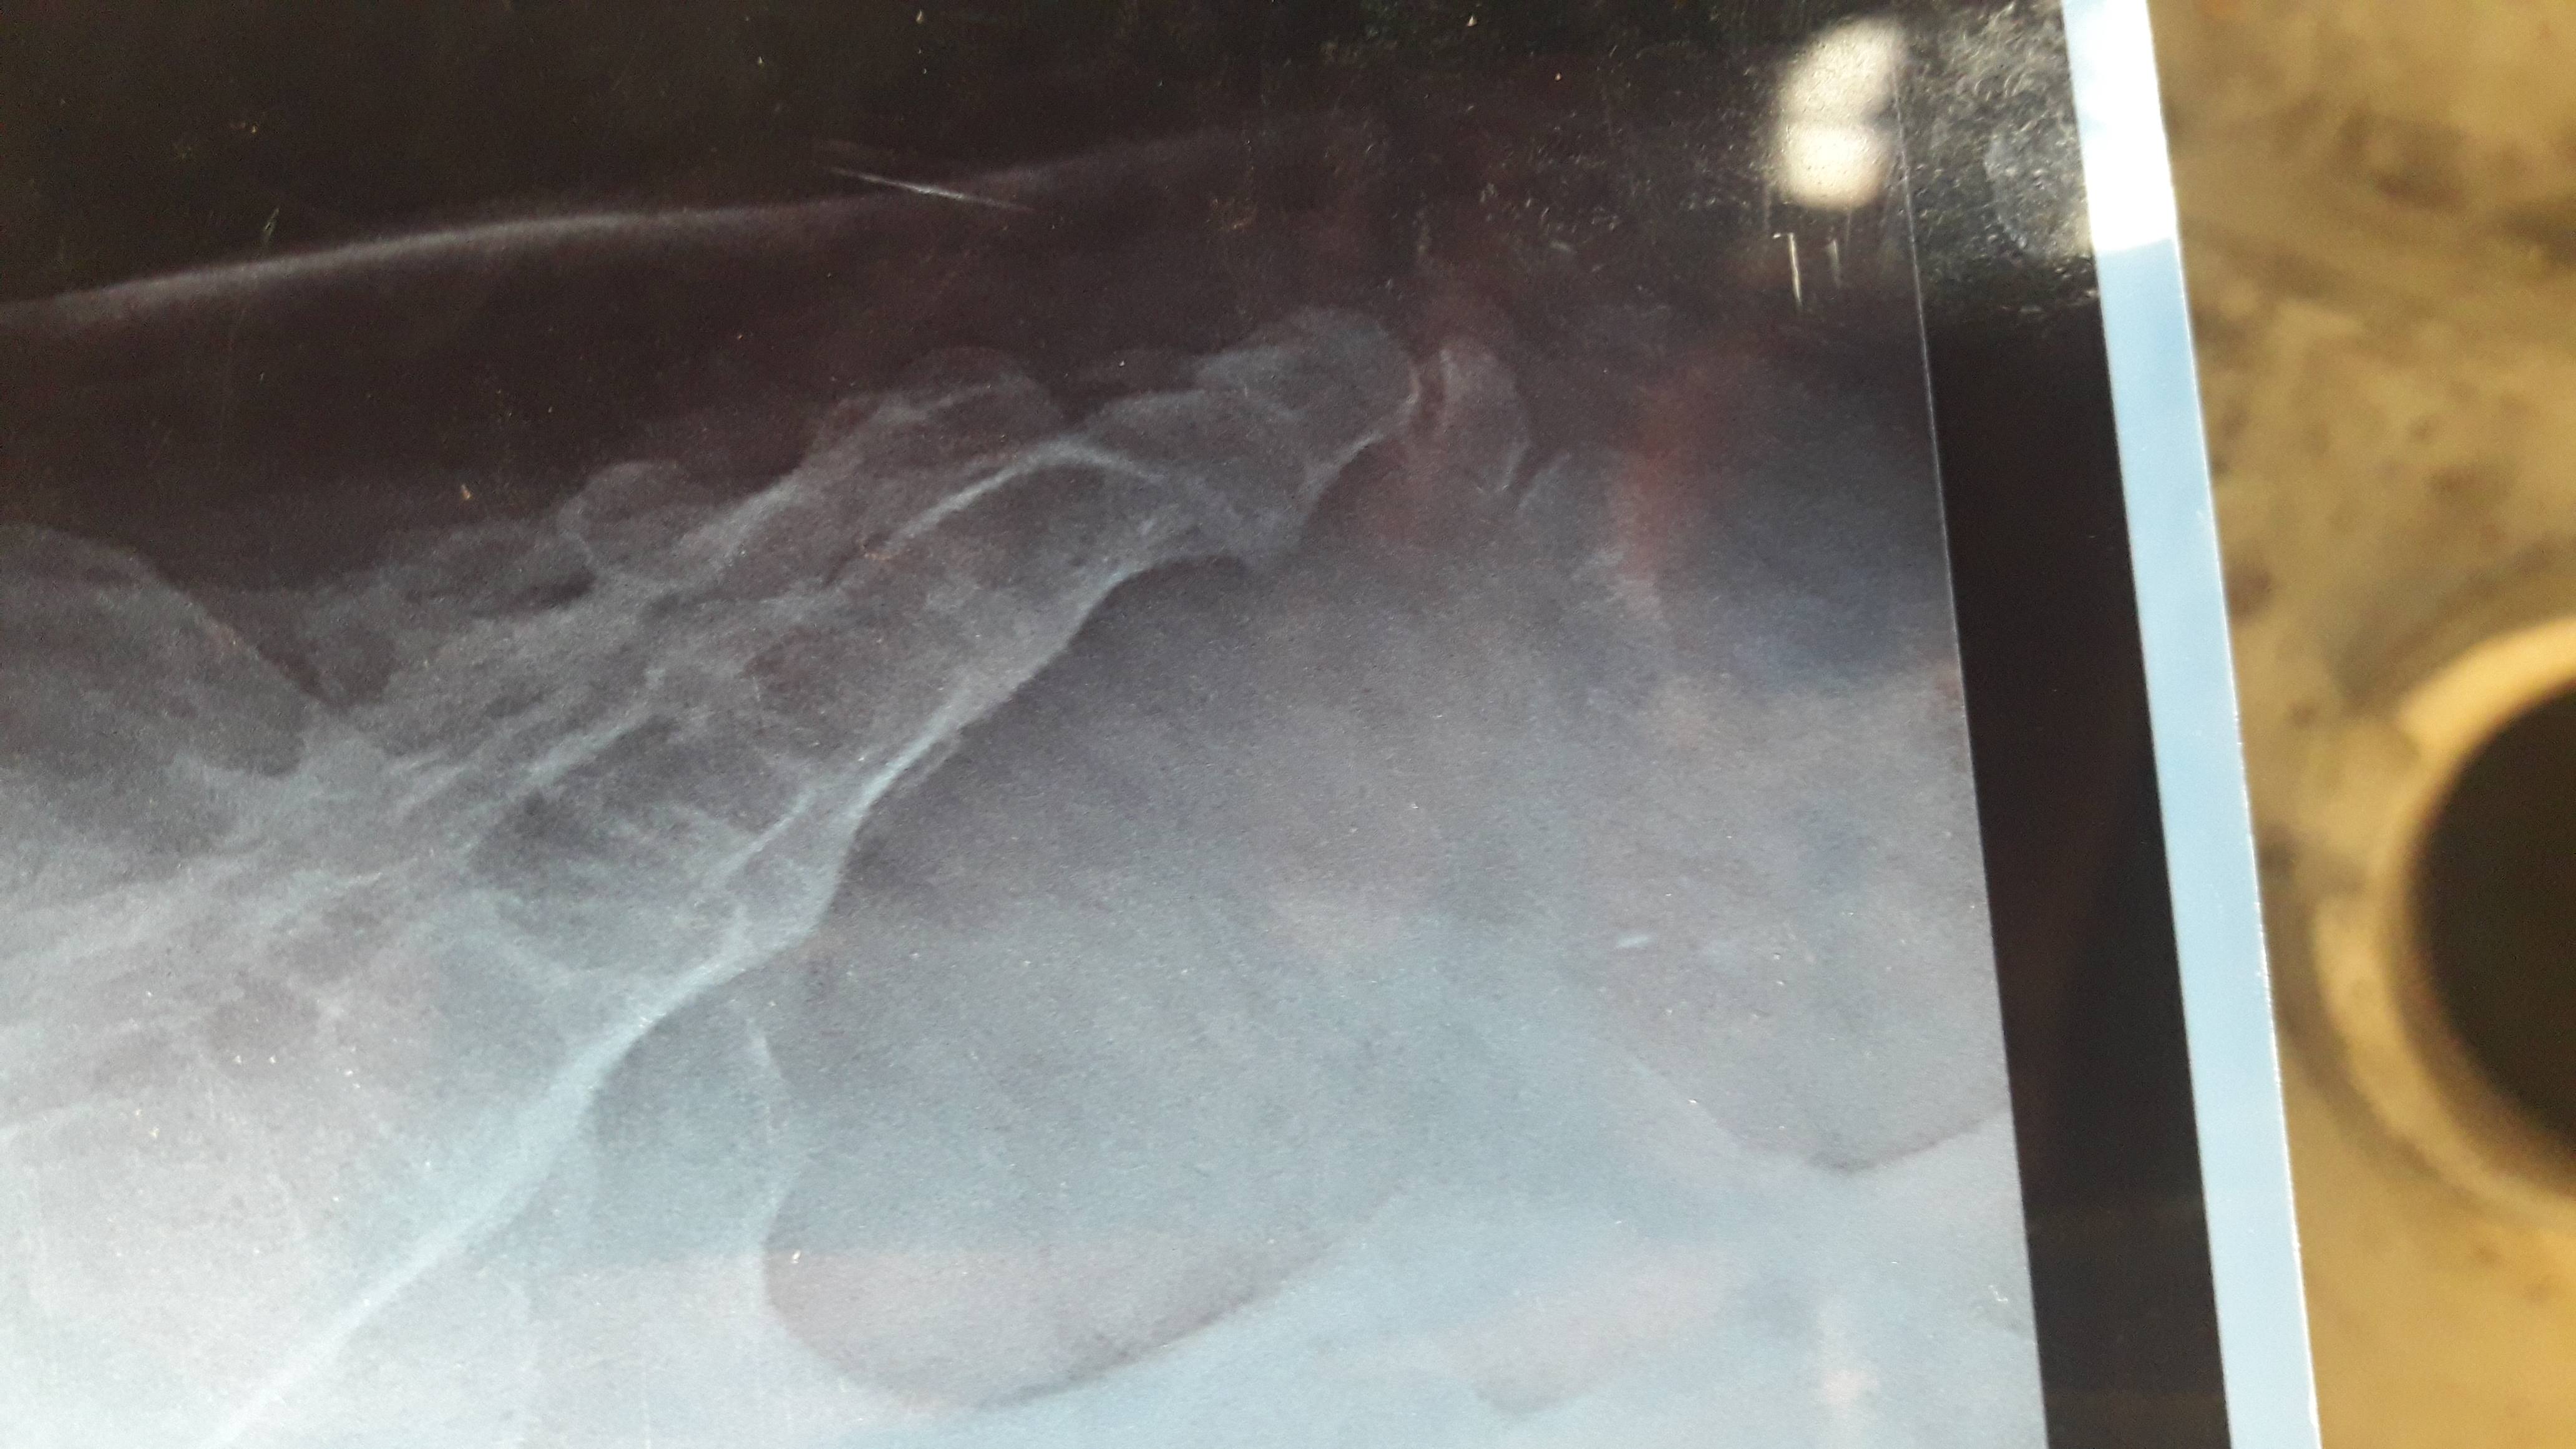

Coccyx fracture healing duration